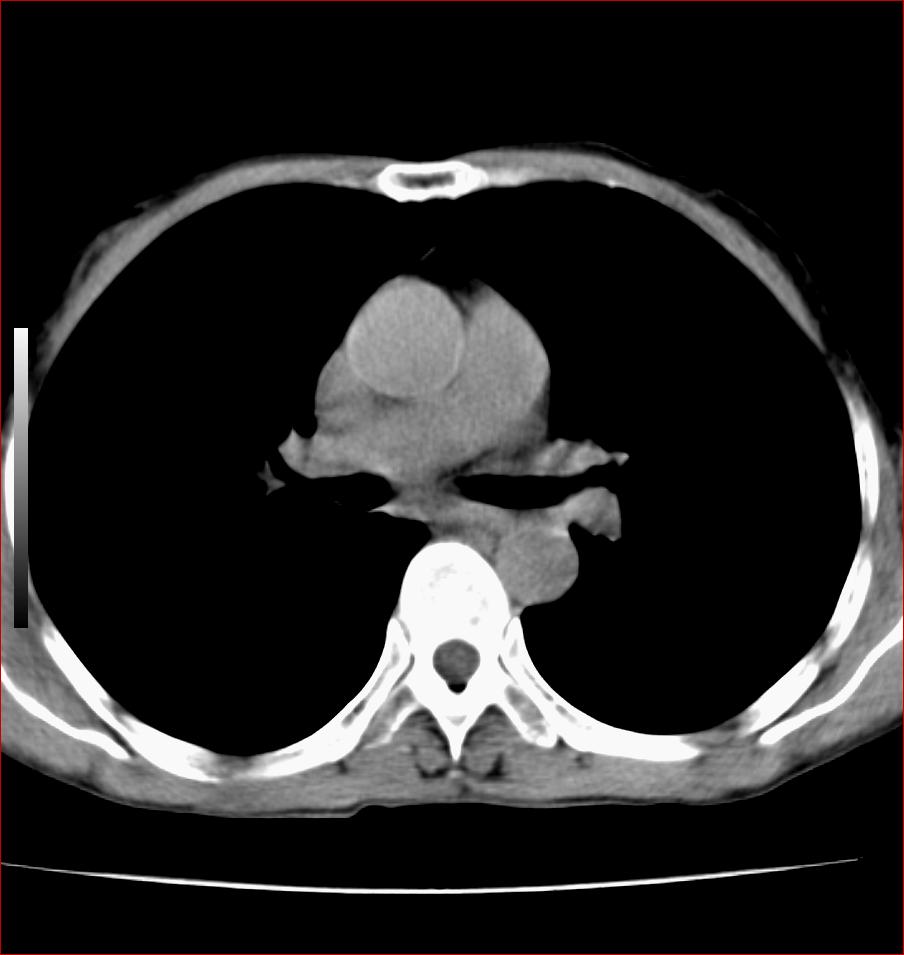

标题: CT17110:F56Y,纵隔囊肿;胸腺?淋巴?请各位老师看看 [打印本页]

标题: CT17110:F56Y,纵隔囊肿;胸腺?淋巴?请各位老师看看

女性患者 56 咽痛伴声嘶10+天入院。

右上纵隔囊性占位性病变;考虑支气管囊肿可能。

病变紧贴气管右壁,两者相互压迫,考虑支气管囊肿!

见相互挤压征,考虑气管囊肿,建议ct增强扫描

纵隔前肠性囊性,支气管囊肿可能性大